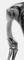

При рентгенологическом исследовании в случаях О. обнаруживается участок разрежения костной ткани без четких контуров. В процессе динамического наблюдения он увеличивается в объеме, приводя к частичному или полному исчезновению участка или всей кости (например, фаланги пальца). При неравномерном течении процесса О. может образовываться секвестроподобная тень, которая в дальнейшем также подвергается рассасыванию.

Остеолиз суставных концов длинных трубчатых костей наблюдается при ряде неврогенных артропатий и может сопровождаться развитием околосуставных оссификатов. Как правило, при О. отсутствует периостальная реакция, что может служить дифференциально-диагностическим признаком.